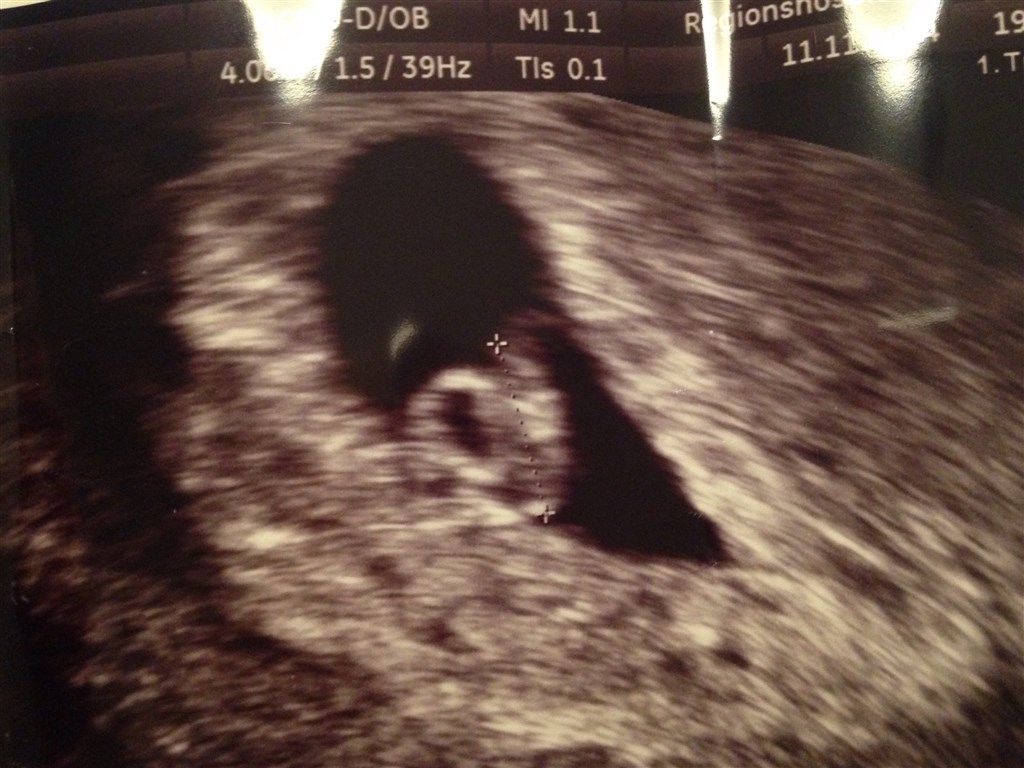

Men jeg var igår til tidlig tryghedsscanning er 7+3 idag, og er fuldstændig sikker.. Kunne også allerede teste 3+4..

Scanningen igår, gik egentlig også nogenlunde.. Efter noget tid siger hende som scanner at det ser rigtig godt ud, gudskelov

Der er fin hjerteblink

og at den er lige så stor som den skal være, 6 uger..